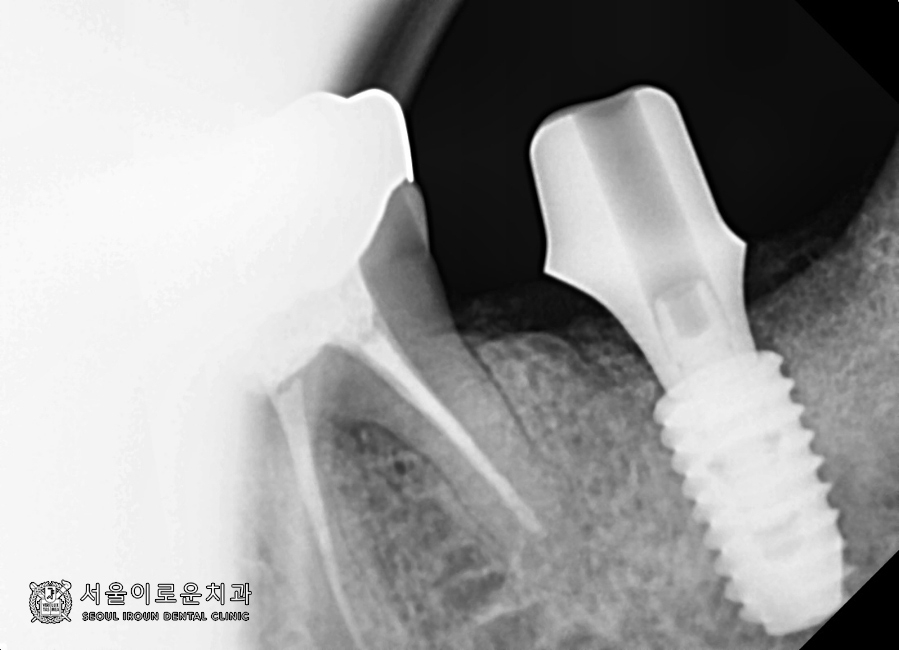

가장 먼저, 발치 후

염증조직을 깨끗이 제거한 뒤

뼈이식을 동반한 임플란트를 식립하였습니다!

* 염증조직이 남아 있을 경우,

뼈이식 뒤 골유착에 방해를 줄 수 있어

사전에 말끔히 제거하는 것이

필요합니다.

2달반 후

뼈와 임플란트가 잘 붙었는지 확인하는

osstell beacon이라는 장비를 이용하여

isq(골유착정도)를 측정하였는데요.

안정적이라는 것을 확인하고

오른쪽 아래 첫번째 큰 어금니(#46)에

성공적으로 보철과정을

마무리 하였습니다. 😄